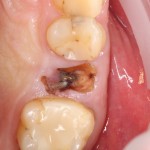

В общем, так и получилось. Уж не помню, почему я наобещал пациентке, что мы поставим ей имплантаты одновременно с остеопластикой. Но я наобещал. И, когда увидел клиническую картину в полости рта:

у меня появились серьезные сомнения, смогу ли я выполнить своё обещание. Вот только не спрашивай меня «Вот чо, сложно было по КЛКТ посмотреть?». Я же не спрашиваю тебя, где ты был в 2013 году, и сделал ли ты домашку. Но, в целом, план операции у нас не поменялся. Как и было оговорено, мы проведем остеопластику с одновременной имплантацией в боковом участке нижней челюсти справа.

Кстати, обрати внимание на ширину альвеолярного гребня (левая картинка). Она чуть меньше 3 мм. Это объясняет, почему я засомневался в возможности установки имплантатов одновременно с остеопластикой. Понятно и без КЛКТ.